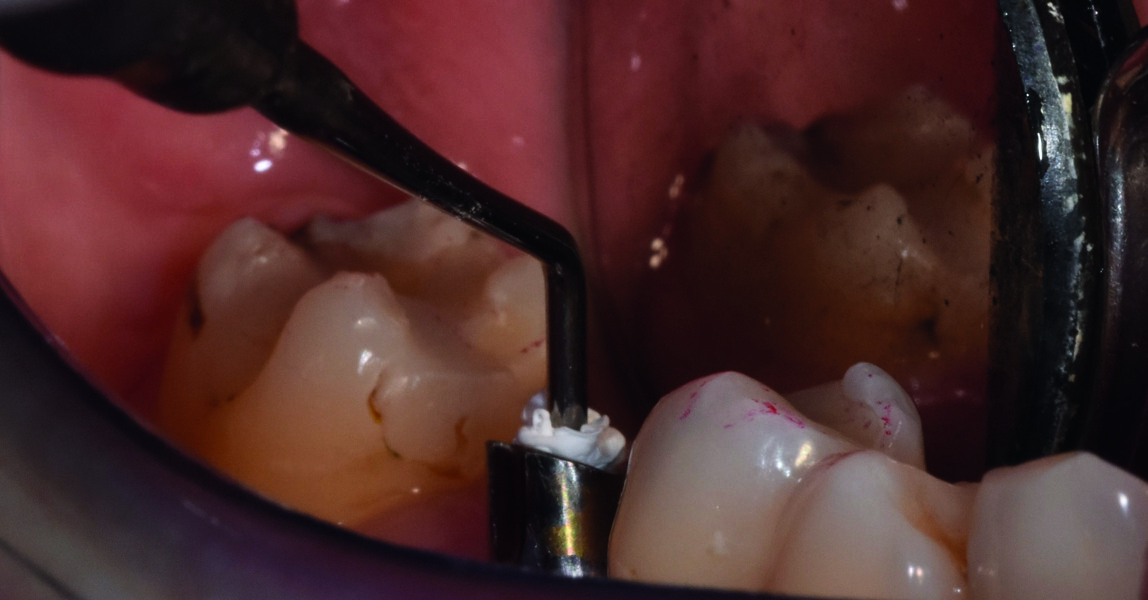

Essayage du guide en bouche.

Vérification de sa stabilité et de sa parfaite adaptation grâce aux fenêtres d’inspection.

Préparation du lit implantaire Passage du foret pilote correspondant à celui défini lors de la planification. Introduire le foret dans la douille avant de mettre en rotation ce dernier, ensuite utiliser une vitesse de forage comprise entre 700 à 800 tours/minute et sous irrigation. Ensuite utiliser des forêts à étage, afin de ne pas dévier de l’axe planifié.

Fig. 11 : Vérification de sa stabilité et de sa parfaite adaptation en bouche grâce aux fenêtres d’inspection.